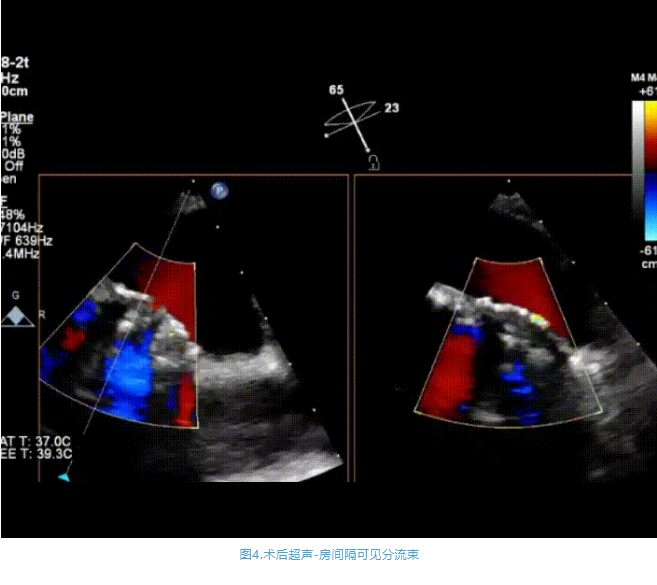

術(shù)中首先在局麻下穿刺股動脈、股靜脈,完成心導(dǎo)管檢查評估后轉(zhuǎn)為全麻,在食道超聲引導(dǎo)下穿刺房間隔,穿刺成功后將加硬導(dǎo)絲送入左上肺靜脈建立軌道,根據(jù)患者病情行球囊預(yù)擴張后植入6mm孔徑房間隔造孔支架,經(jīng)透視及食道超聲評估支架左右盤展開良好,夾持于房間隔兩側(cè),固定穩(wěn)定、位置良好,食道彩超顯示房水平右向左為主分流,分流孔直徑符合預(yù)期大小,心導(dǎo)管檢查評估達到預(yù)期效果,釋放造孔支架。術(shù)后12h患者下床活動,恢復(fù)順利,擬于近日完善術(shù)后評估后出院。

心房分流術(shù)是通過器械制造穩(wěn)定可控的心房間分流,適應(yīng)證包括藥物治療效果不佳的左心衰或肺動脈高壓右心衰。本例患者為肺動脈高壓右心衰,術(shù)中成功放置MicroFlux®造孔支架在房間隔理想位置上,創(chuàng)造穩(wěn)定可控的心房間分流(此例患者以右向左分流為主),在不顯著增加左心負擔(dān)的情況下,有效降低患者右心房壓力、緩解體循環(huán)淤血,增加左心輸出量,改善患者癥狀、活動耐力和生存質(zhì)量。同時,國內(nèi)外也已經(jīng)開展多項房間隔造孔支架在射血分數(shù)保留、射血分數(shù)中間值和射血分數(shù)降低的左心衰患者中的臨床研究,結(jié)果顯示對于經(jīng)過充分的規(guī)范化藥物治療后仍控制不佳的患者,心房分流術(shù)可改善患者的癥狀及生存質(zhì)量?! ?/p>